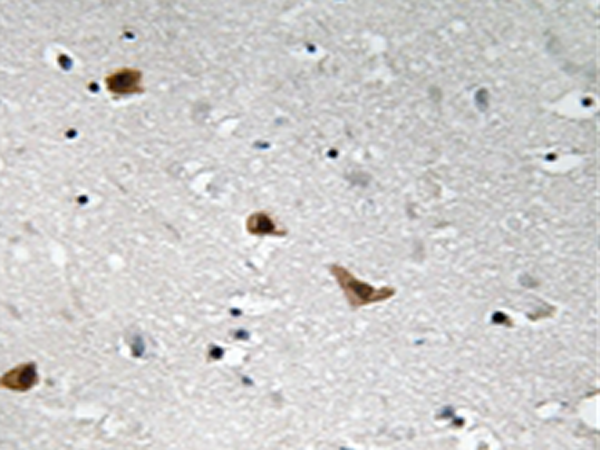

IHC |

IHC positive control: |

Human brain tissue |

IHC Recommend dilution: |

50-100 |